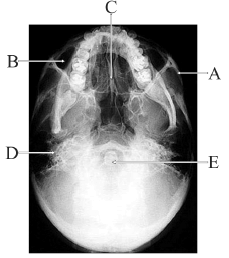

O domínio da anatomia radiográfica é fundamental para identificações de alterações e patologias que comprometem as estruturas mineralizadas da região de cabeça e pescoço.

A grande abertura através do osso occipital localizada no centro da fossa posterior do neurocrânio está indicada por E.